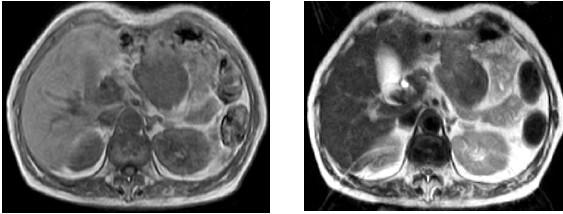

we report a mesenteric desmoid tumor in a 73-years-old woman who had undergone total gastrectomy reconstructed with jejunal pouch interposition for gastric carcinoma. After 1 year, a tumor was originating from mesentery of the interposed jejunal pouch was identified, and the patient underwent resection of the large mass which was found to invade pancreas. Histological examination revealed desmoid tumor.

我们报告了一名73岁女性的肠系膜韧带样瘤,该患者因胃癌接受了空肠间置代胃全胃切除术。1年后,发现起源于间置空肠襻系膜的肿瘤,患者接受了大块肿物切除,发现该肿物侵犯了胰腺。组织学检查显示为韧带样瘤。